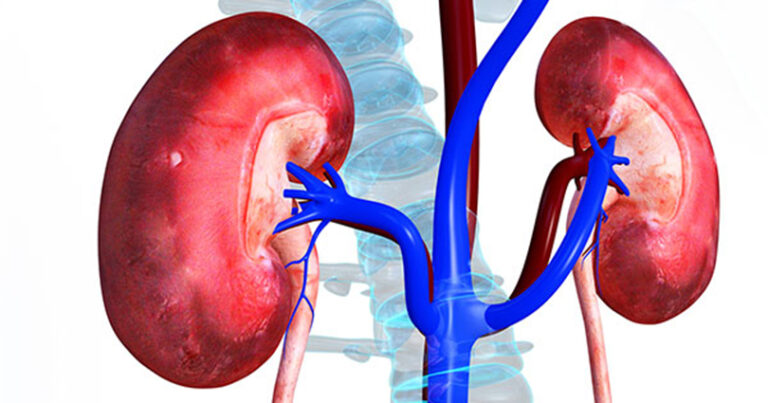

काठमाडौँ — मिर्गौला उपचारमा सबैको समान पहुँच र सुरक्षित चिकित्सकीय अभ्यास’ भन्ने नाराका साथ आज विश्व मिर्गौला दिवस मनाइँदै छ । विभिन्न कार्यक्रम गरी बर्षेनि मार्च १४ गते यो दिवस मनाइँदै आएको छ ।

विश्वभर नै मिर्गौला रोगको प्रकोप बढिरहेको परिप्रेक्ष्यमा रोगको पहिचान तथा उपचार र रोकथामका महत्त्वपूर्ण उपायहरूबारे सबैलाई सचेत गराउने उद्देश्यले मिर्गौला दिवस मनाइन्छ । यो वर्ष पनि नेपालमा विभिन्न कार्यक्रम गरी विश्व मिर्गौला दिवस मनाइँदै छ ।

विभिन्न संस्थाबाट विभिन्न कार्यक्रमसहित हुँदै आएको कार्यक्रम यसपटक भने अङ्ग प्रत्यारोपण समाज नेपाल र नेपाल प्रत्यारोपण सोसाइटी एउटै भएपछि पहिलो पटक संयुक्त रूपमा कार्यक्रम आयोजना गरेको छ ।